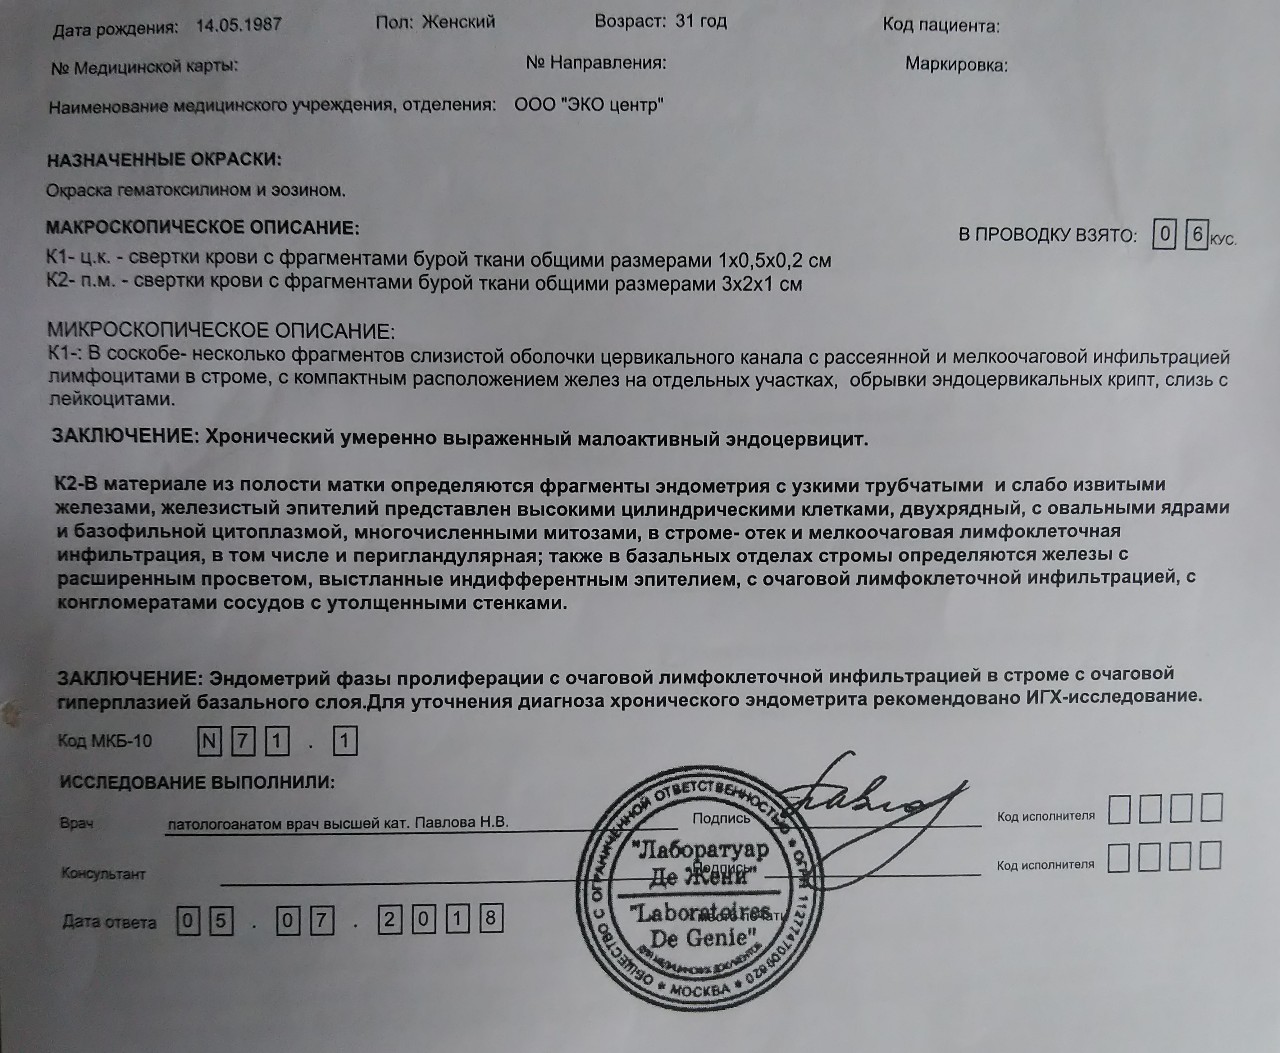

Медицинская диагностика: Гиперплазия эндометрия на УЗИ

Раздел: Мудрость в объективе